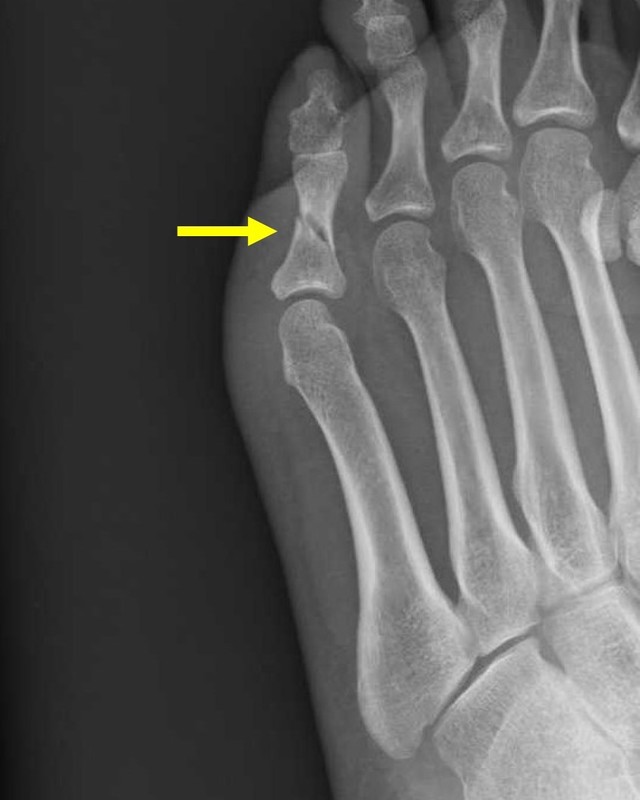

単純レントゲン撮影

X線(エックス線)を体にあてる(照射する)ことにより、画像化する検査です。空気は黒く、骨は白く見えます。一般的に『レントゲン撮影』と呼ばれます。